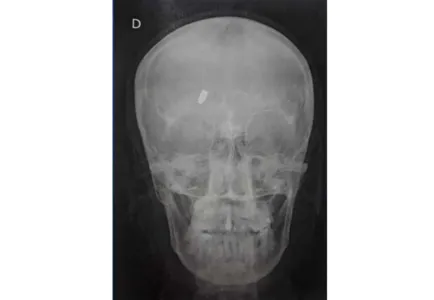

No local, uma profissional de saúde informou à mulher que ela havia levado um tiro e que a munição estava alojada. A princípio, a munição seria de calibre 22.

Às 20h30, a Polícia Militar (PM) foi acionada para comparecer na unidade hospitalar. Aos agentes, a paciente disse que não sabia de onde veio o tiro.